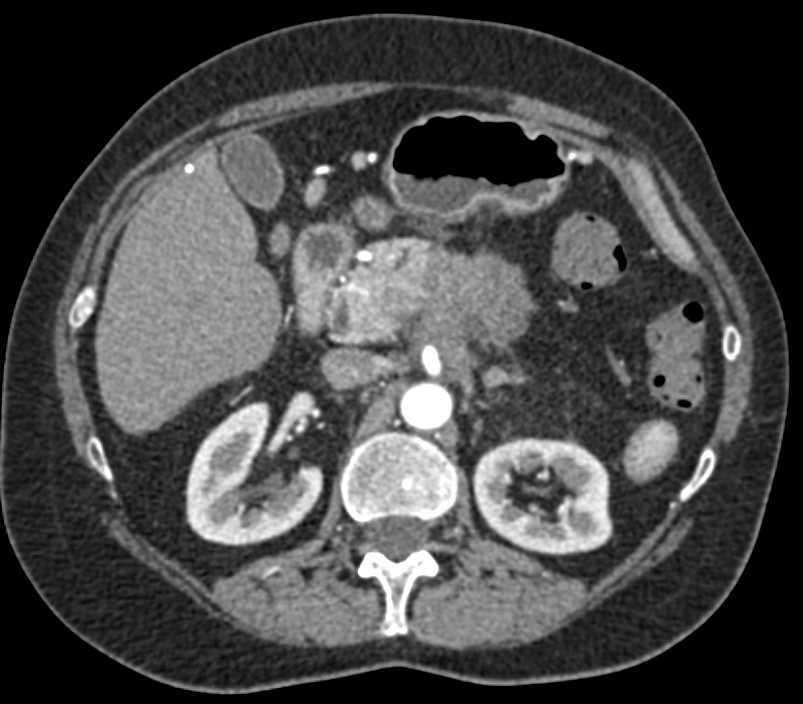

Pancreatic Adenocarcinoma Encases the Portal Vein (PV) and Occludes the Splenic Vein with Cinematic Rendering